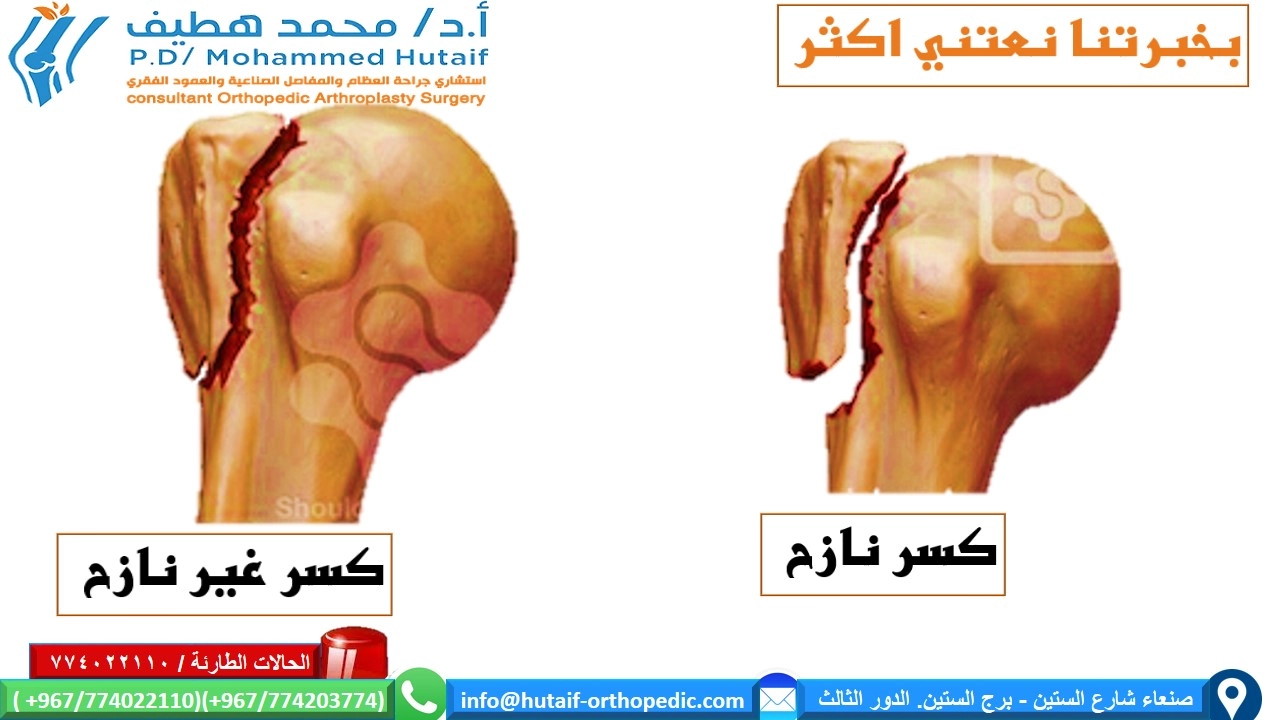

تصنيف الكسور (تصنيف نير Neer Classification)

يُعد تصنيف نير أحد أكثر الأنظمة استخدامًا لتقييم كسور عظم العضد القريب. يقسم هذا التصنيف الكسر بناءً على عدد الأجزاء الرئيسية المتأثرة (رأس العضد، الحدبة الكبرى، الحدبة الصغرى، وجسم عظم العضد) ومدى إزاحتها. يُعتبر الجزء "مُزاحًا" إذا كان هناك إزاحة تزيد عن 1 سم أو زاوية تزيد عن 45 درجة:

* جزء واحد (One-part): جميع الشظايا في مكانها أو بإزاحة بسيطة جدًا.

* جزأين (Two-part): جزء واحد مُزاح بشكل كبير (مثل كسر في العنق الجراحي أو الحدبة الكبرى).

* ثلاثة أجزاء (Three-part): جزأين مُزاحين بالنسبة للثالث.

* أربعة أجزاء (Four-part): جميع الأجزاء الأربعة مُزاحة. يحمل هذا النمط أعلى خطر للإصابة بالنخر اللاوعائي.

يساعد هذا التصنيف الأستاذ الدكتور محمد هطيف في تحديد شدة الكسر وتوجيه خطة العلاج المناسبة لكل مريض.